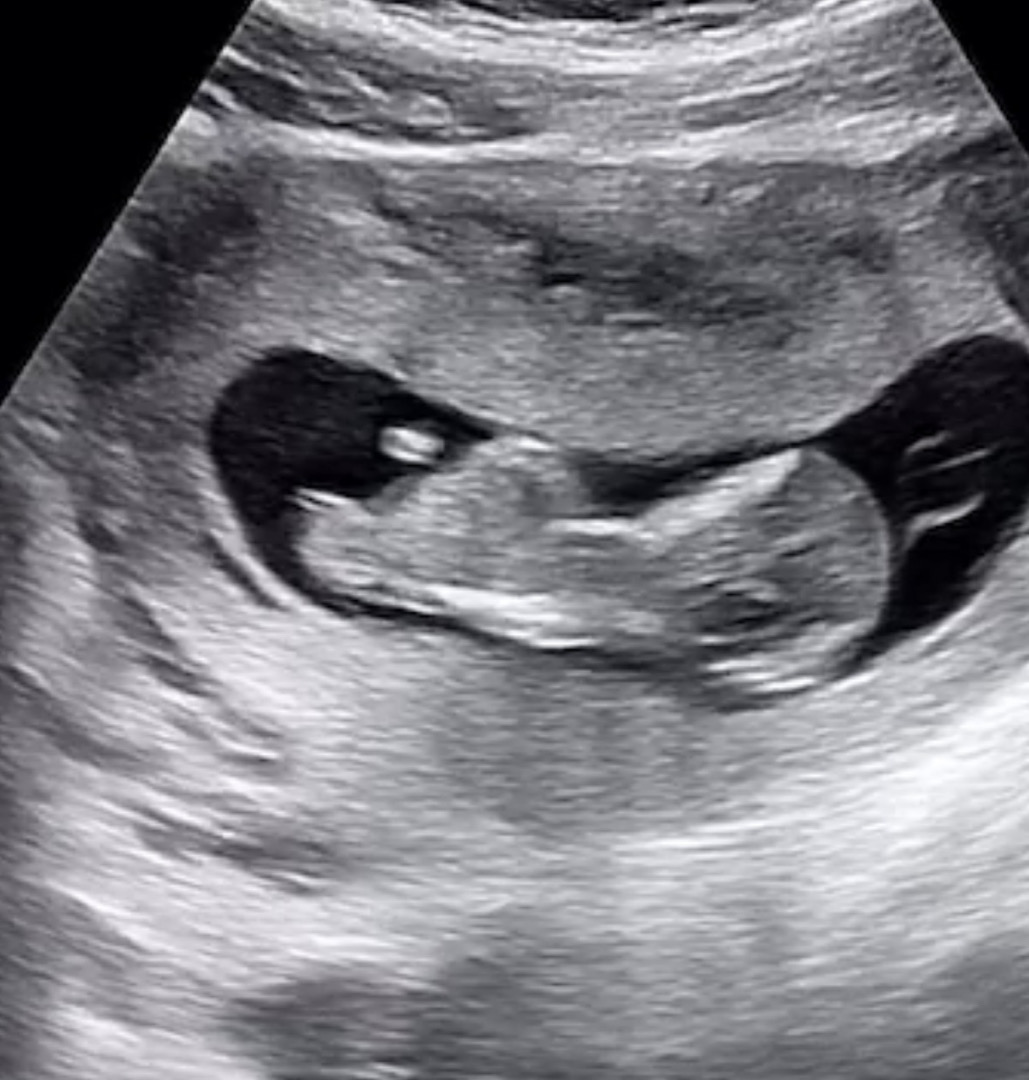

오늘 1차 기형아 검사 하구왔네용(각도법)

둘째 11주 6일 정도 되고 1차 기형아 검사 아무문제없이 잘 보고왔네요❤️!! 저희 선생님이 짧게 보시는 스타일이라ㅠㅜ각도법도 자세히 모르겠네요... 첫째 태몽(엄마/할머니: 큰잉어꿈) 둘째 태몽 남편 : 하얀나비 수천마리 아내 : 초록색 예쁜뱀 혹시 각도는 어떻게 보이시나요!!ㅎㅎ이미 정해진 운명이지만..첫째가 아들이라 둘째는 딸이긴 내심 원합니다 하하..ㅎㅎㅎ재미로만 봐주세요

우리 첫째랑 촘파가 비슷하네요 끝에 갈라지면 딸이라던데 ㅎㅎ 딸같은데용 ?

장꾸맘님도 딸 한표주시고 ㅎㅎㅎ 저도 위에서 찍은거 봤는 생식기가 확연히 갈라져있더라구요 ㅎㅎㅎ제발 딸이길 기도해봅니다👧🏻

딸같아요 ㅎㅎ의사쌤이 별말씀 없으신가요?저도 11주6일차에 병원갔는데 딸로 알고있으라고 하시더라구요 ㅎㅎ